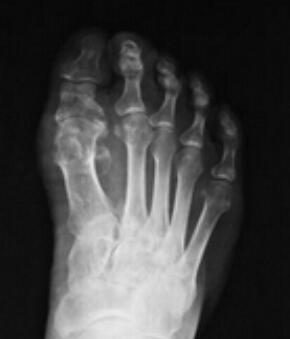

(图:治疗前鲁先生的x光图,可明显看出拇指关节肿大、外翻)

X线示:左足跖骨骨头处出现溶骨性缺损。